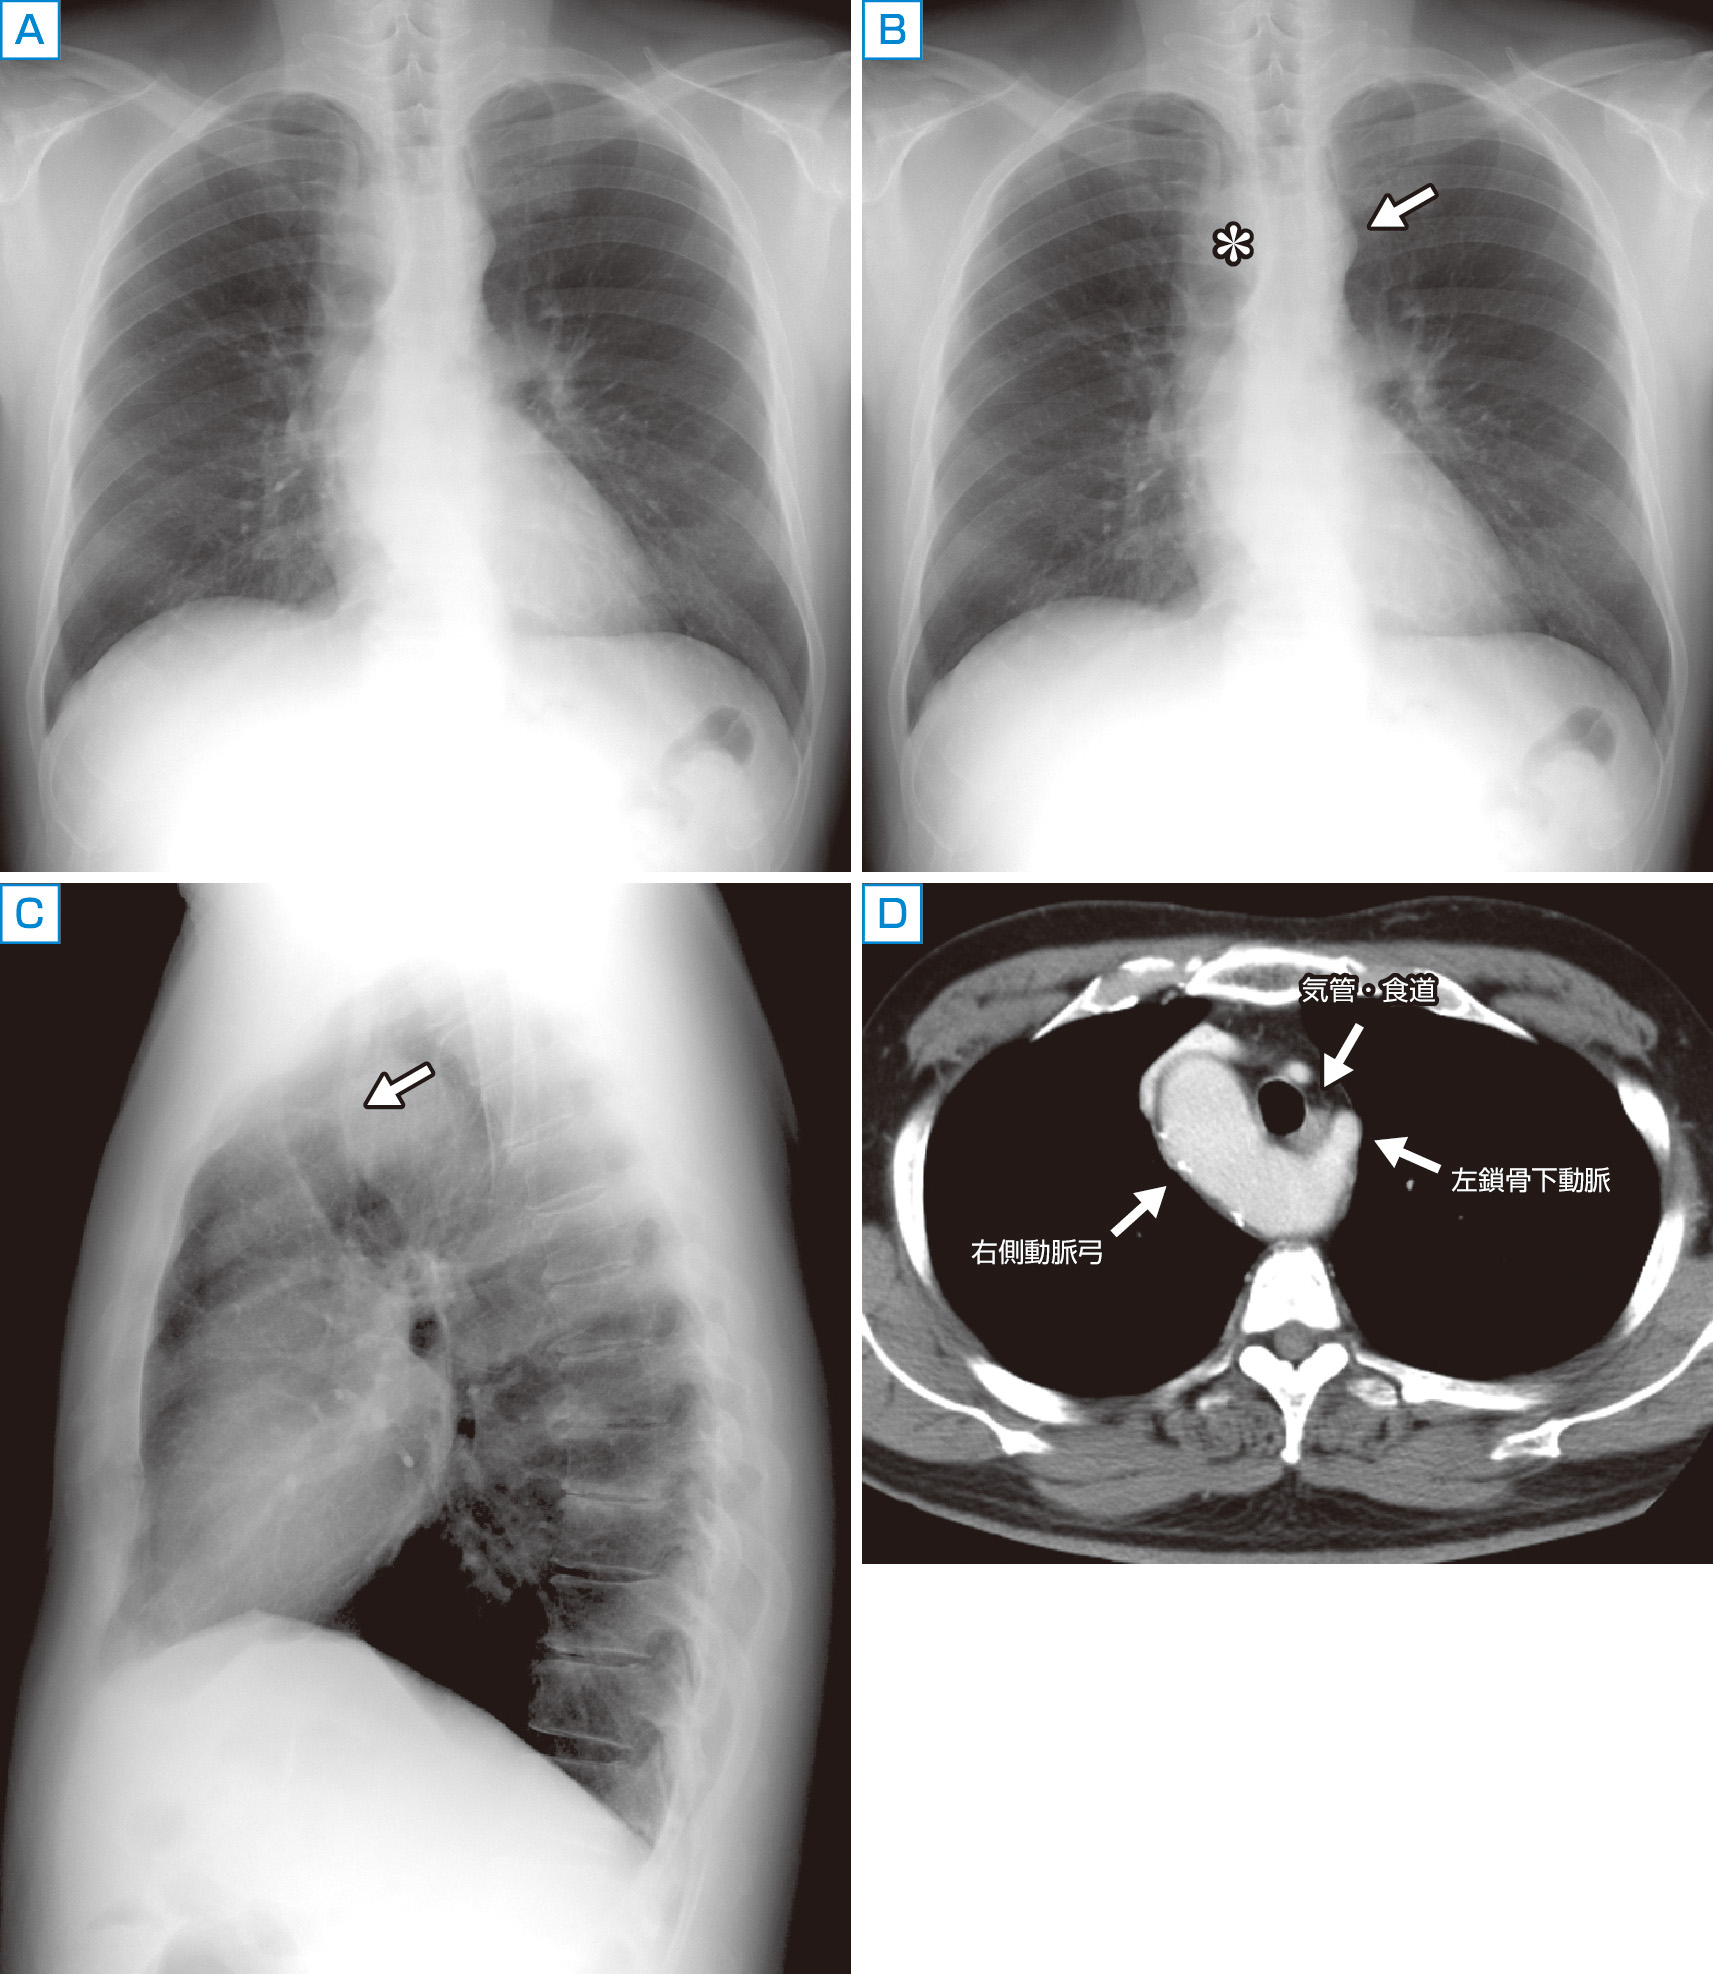

まず目につくのは下行大動脈の蛇行であるが,その上方,いわゆる左第1弓の陰影が成人男性にしては奇妙に小さい (B).また気管右側の陰影が通常より幅広く,白くみえる (B*).よくみると気管は左に若干圧排されている.側面像では気管が前方に圧排されている (C矢印).CTが撮影され,異所性左鎖骨下動脈を伴う右側大動脈弓と診断された (D).

胎生期において腹側大動脈と左右1対の背側大動脈を結ぶ左右6対の大動脈弓が生じ,これらが退縮していくことで大動脈および腕頭動脈,総頸動脈,鎖骨下動脈が形成される.正常では左第4大動脈弓と左背側大動脈が大動脈弓になるが,左側が退縮し右側が遺残すると右側大動脈弓になる.右側大動脈弓では本症例のように左鎖骨下動脈が大動脈弓遠位から分岐し,気管・食道の背側を通るタイプが最も多く,血管輪による症状を呈することがある.対して弓部の血管分岐が正常の左大動脈弓と鏡像であるタイプ (左腕頭動脈,右総頸動脈,右鎖骨下動脈の順に分岐するタイプ) では先天性心疾患を合併することが知られている.本症例でみられた気管の変位は異所性左鎖骨下動脈によるものであった.気管の変位や狭窄は悪性腫瘍や甲状腺腫などで起こることもあり見逃さないようにしたい.